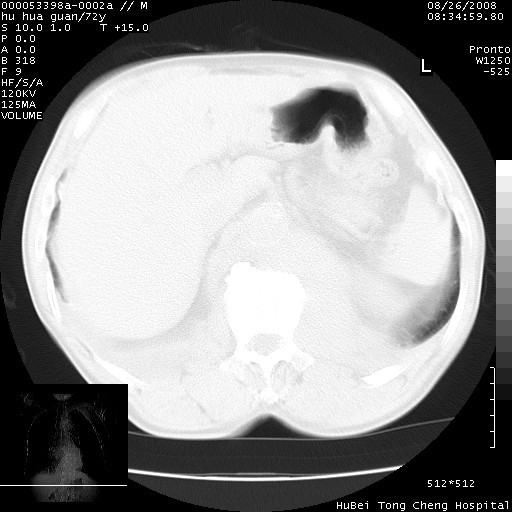

胸腔b超:胸腔积液。胸膜腔抽水化检:l 81%。

可以明确的说。肯定不是主动脉夹层破裂出血!考虑为淋巴瘤或间叶组织来源的恶性肿瘤可能性大。右肺小结节建议薄层观察,如能发现恶性征象,那椎前改变就考虑为转移所致。至于双侧少量胸水乃静脉血回流受阻所致。

2、右下肺背段少许炎症,双侧胸腔积液,右下肺纤维索条。

后纵隔占位,降主动脉前移位;双侧胸腔积液;应排外食管病变侵犯血管可能;

建议排除结核引起的冷脓肿。